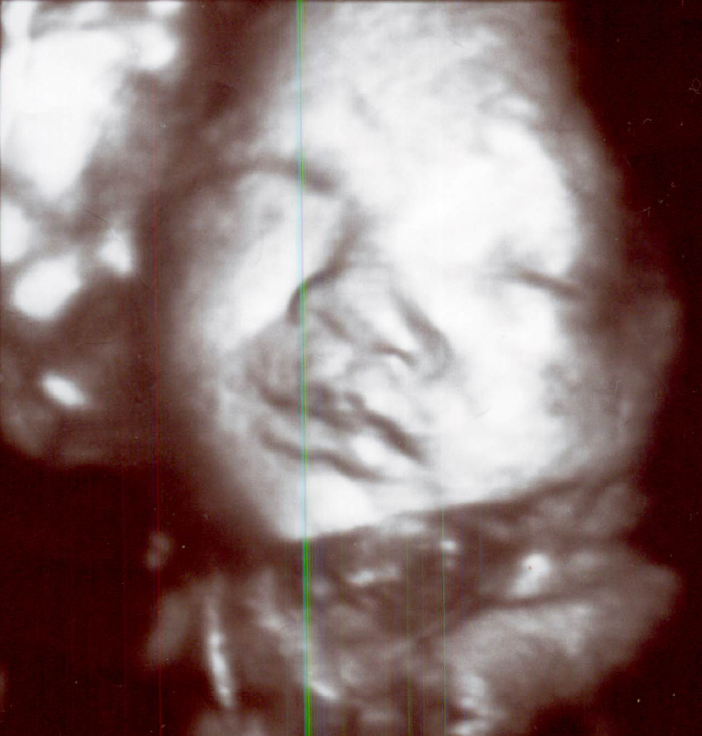

妊娠中期以降になると、顔立ちが良く見えます。

7~8か月以降になると、特に、ふっくらした可愛い顔立ちが見えます。

3D,4Dでは特に赤ちゃんの顔が見えると嬉しいです。普段は

ウトウトと静かに寝ている感じですが、たまに

ニコッとしたり

機嫌の悪そうな顔をすることもあります。又たまに目を開けたり、眼をパチパチすることもあります。